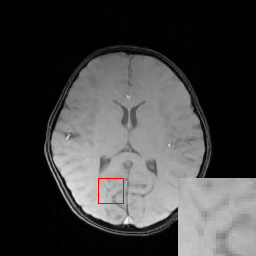

Figure 6: We show the reconstruction results of our DECN model with local area magnification. We also show the reconstruction error for our DECN model under different guide module in the last row.

We evaluate the proposed DECN framework using PSNR and SSIM (structural similarity index) [30] as quantitative image quality assessment measures. We give the quantitative reconstruction results of all the test data on different under-sampling patterns and different under-sampling ratios in Table II. We show the Cartesian 30%percent3030\% under-sampling mask in Figure 6(b) and the Random 20%percent2020\% under-sampling mask in Figure 7(b). We observe that DECN improved all off-the-shelf CS-MRI inversion methods on all the under-sampling patterns. Since the Random mask enjoys the more incoherence than the Cartesian mask with the same under-sampling ratio, the CS-MRI achieves better reconstruction quality on the Random masks. Also, we observe the plain DC-CNN model already achieves good reconstruction accuracy, leaving less structural errors for the error correction module, leading to the limited performance improvement about 0.1 dB on the Random 20%percent2020\% and 30%percent3030\% masks. While for other CS-MRI inversions on various sampling patterns, the improvements are at least 1.5dB or even up to 3.5 dB.

In Figure 6, we show reconstruction results and the corresponding error images of an example from the test data on the 1D 30%percent3030\% under-sampling mask. With local magnification on the red box, we observe that by learning the error correction module, the fine details, especially the low-contrast structures are better preserved, leading to a better reconstruction.